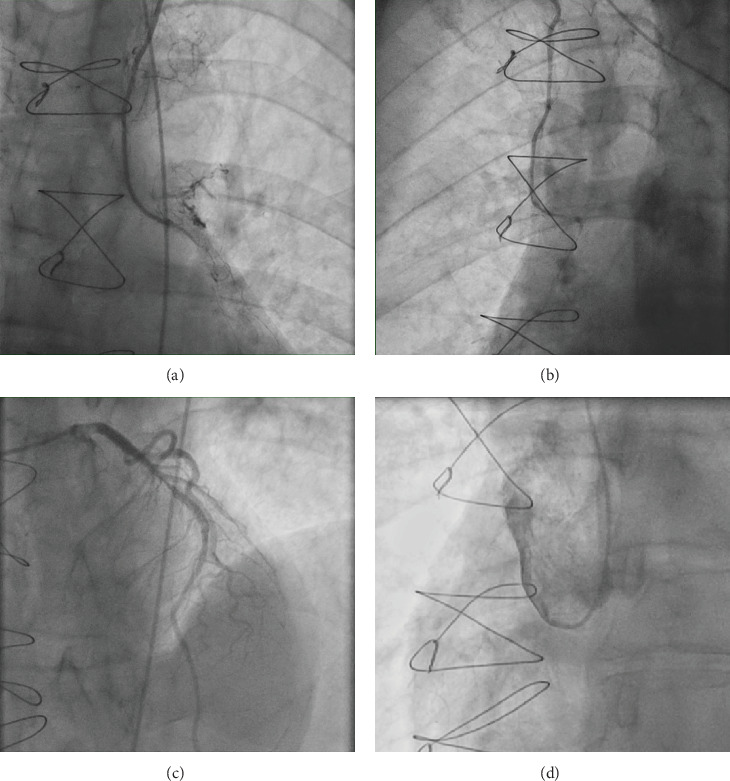

A 67-year-old male presented with non-ST elevation myocardial infarction (NSTEMI) with underlying anomalous origin of the right coronary artery (RCA) and a malignant course between the aorta and pulmonary artery. Previous CABG with LIMA and RIMA grafts had failed, leaving the patient with severe in-stent restenosis (ISR) in the LAD and degenerated, blocked grafts. The patient underwent percutaneous coronary intervention (PCI) to the anomalous RCA, which posed challenges in engagement due to its anomalous course. This case report discusses the complexities of managing such anatomies, emphasizing the role of CT coronary angiography, the difficulty of engaging anomalous arteries, and the techniques used to achieve successful PCI.